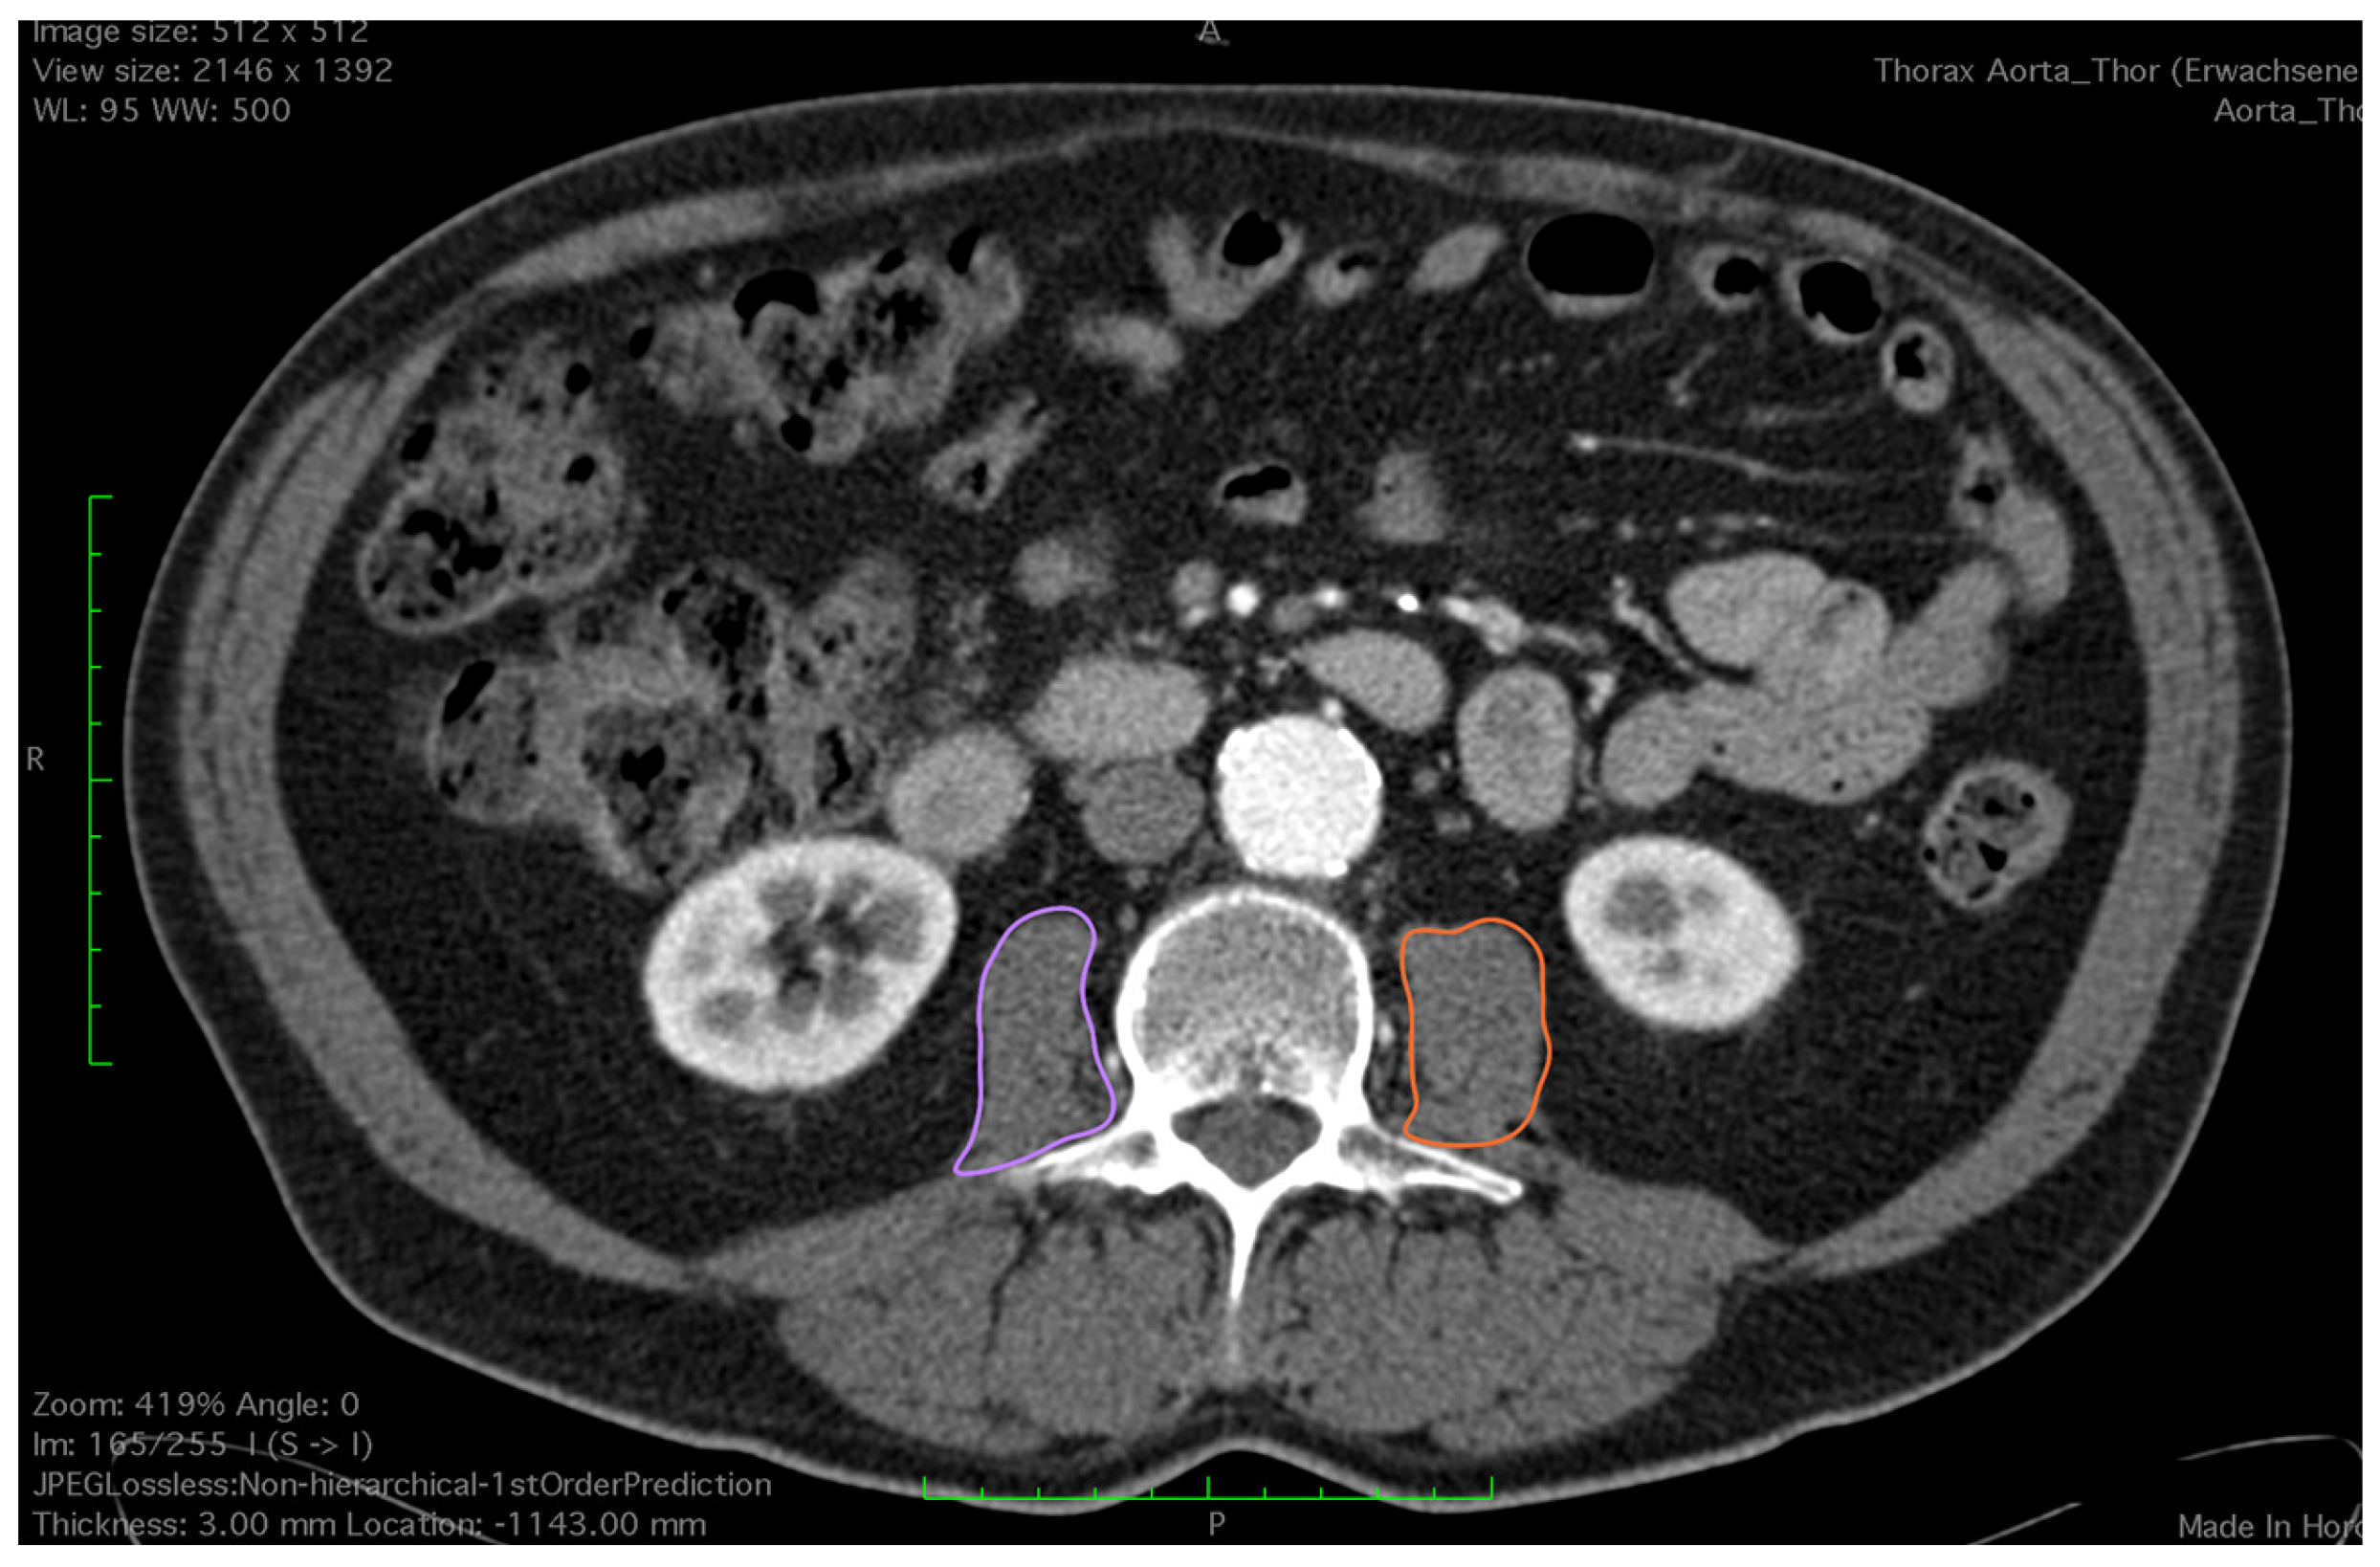

2.2. Assessment of Skeletal Muscle

- Mourtzakis, M.; Prado, C.; Lieffers, J.; Reinman, T.; McCargar, L.; Baracos, V.E. A practical and precise approach to quantification of body composition in cancer patients using computed tomography images acquired during routine care. Appl. Physiol. Nutr. Metab. 2008, 33, 997–1006. [Google Scholar] [CrossRef] [PubMed]

- Shen, W.; Punyanitya, M.; Wang, Z.; Gallagher, D.; St.-Onge, M.-P.; Albu, J.; Heymsfield, S.B.; Heshka, S. Total body skeletal muscle and adipose tissue volumes: Estimation from a single abdominal cross-sectional image. J. Appl. Phsyiol. 2004, 97, 2333–2338. [Google Scholar] [CrossRef] [PubMed]